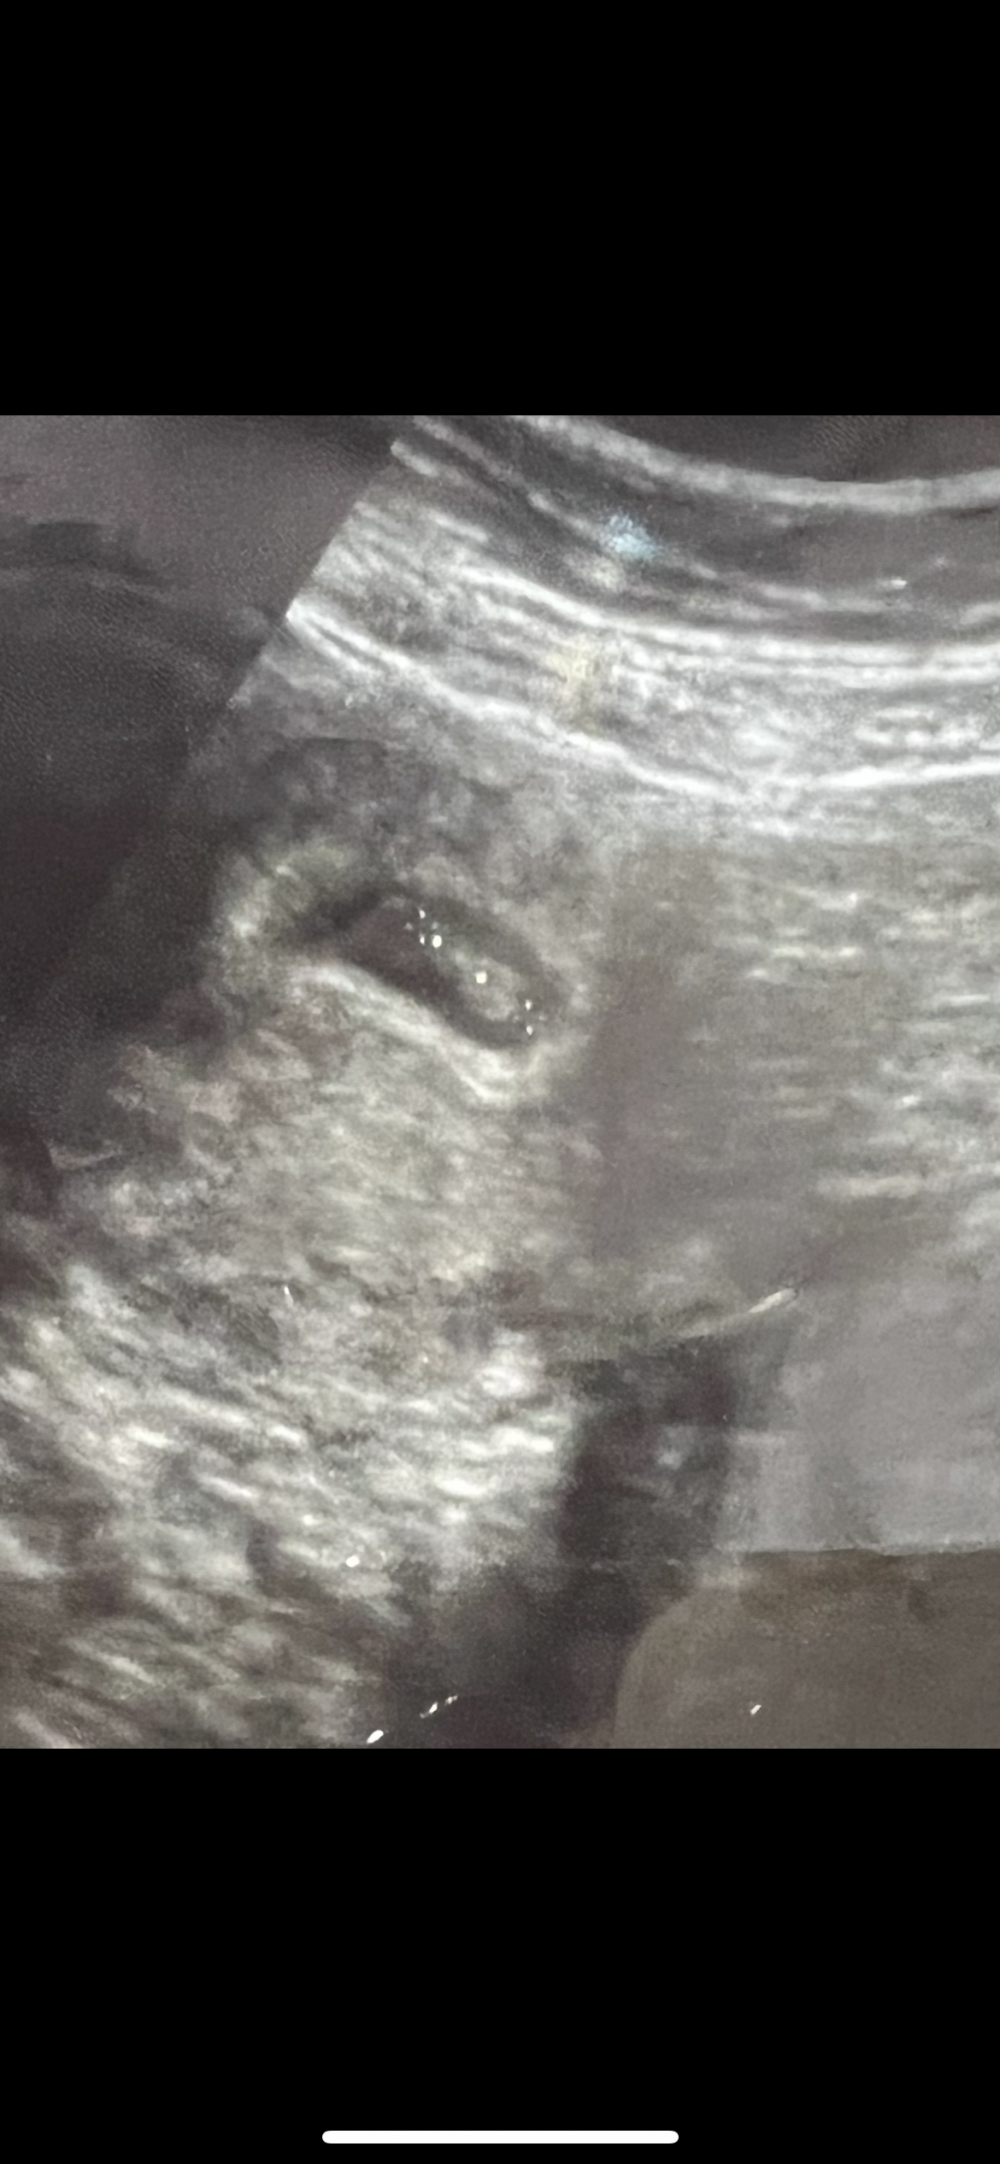

ماشاء الله واضح ولد ع النظرية

هنا بالاسبوع السابع